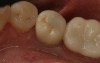

Fig 19. Lingual view of the screw-retained implant crown after placement of the composite “patch.”

Figure 19

Fig 20. Facial view of screw-retained implant crown.

Figure 20

Fig 21. Occlusal view of the screw-retained implant crown.

Figure 21